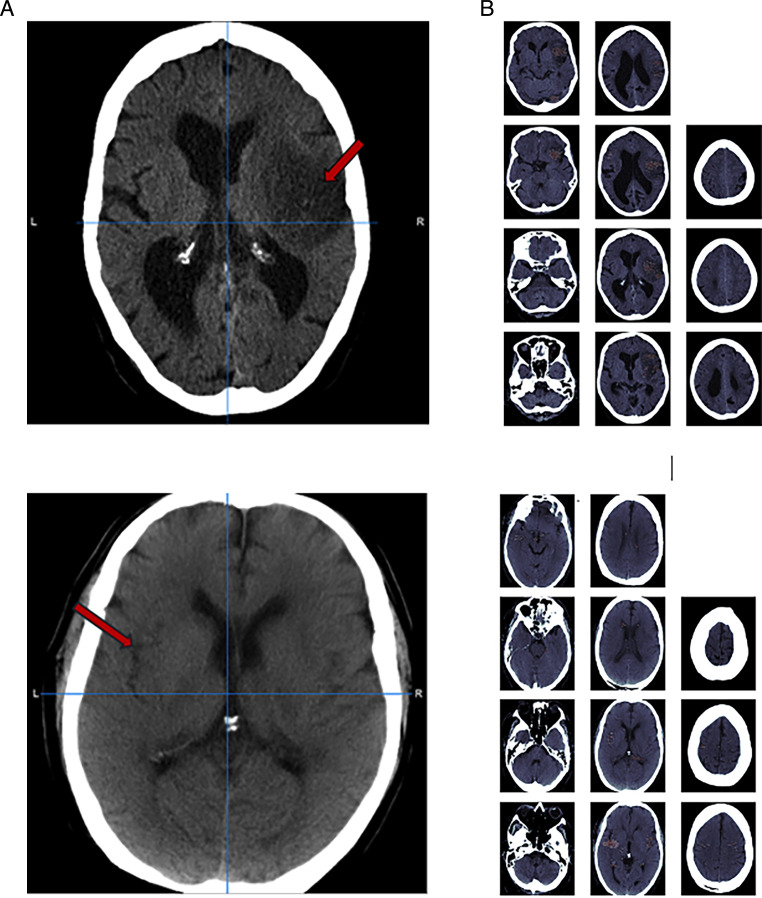

Background: CT is commonly used to image patients with ischaemic stroke but radiologist interpretation may be delayed. Machine learning techniques can provide rapid automated CT assessment but are usually developed from annotated images which necessarily limits the size and representation of development data sets. We aimed to develop a deep learning (DL) method using CT brain scans that were labelled but not annotated for the presence of ischaemic lesions.

Methods: We designed a convolutional neural network-based DL algorithm to detect ischaemic lesions on CT. Our algorithm was trained using routinely acquired CT brain scans collected for a large multicentre international trial. These scans had previously been labelled by experts for acute and chronic appearances. We explored the impact of ischaemic lesion features, background brain appearances and timing of CT (baseline or 24-48 hour follow-up) on DL performance.

Results: From 5772 CT scans of 2347 patients (median age 82), 54% had visible ischaemic lesions according to experts. Our DL method achieved 72% accuracy in detecting ischaemic lesions. Detection was better for larger (80% accuracy) or multiple (87% accuracy for two, 100% for three or more) lesions and with follow-up scans (76% accuracy vs 67% at baseline). Chronic brain conditions reduced accuracy, particularly non-stroke lesions and old stroke lesions (32% and 31% error rates, respectively).

Conclusion: DL methods can be designed for ischaemic lesion detection on CT using the vast quantities of routinely collected brain scans without the need for lesion annotation. Ultimately, this should lead to more robust and widely applicable methods.